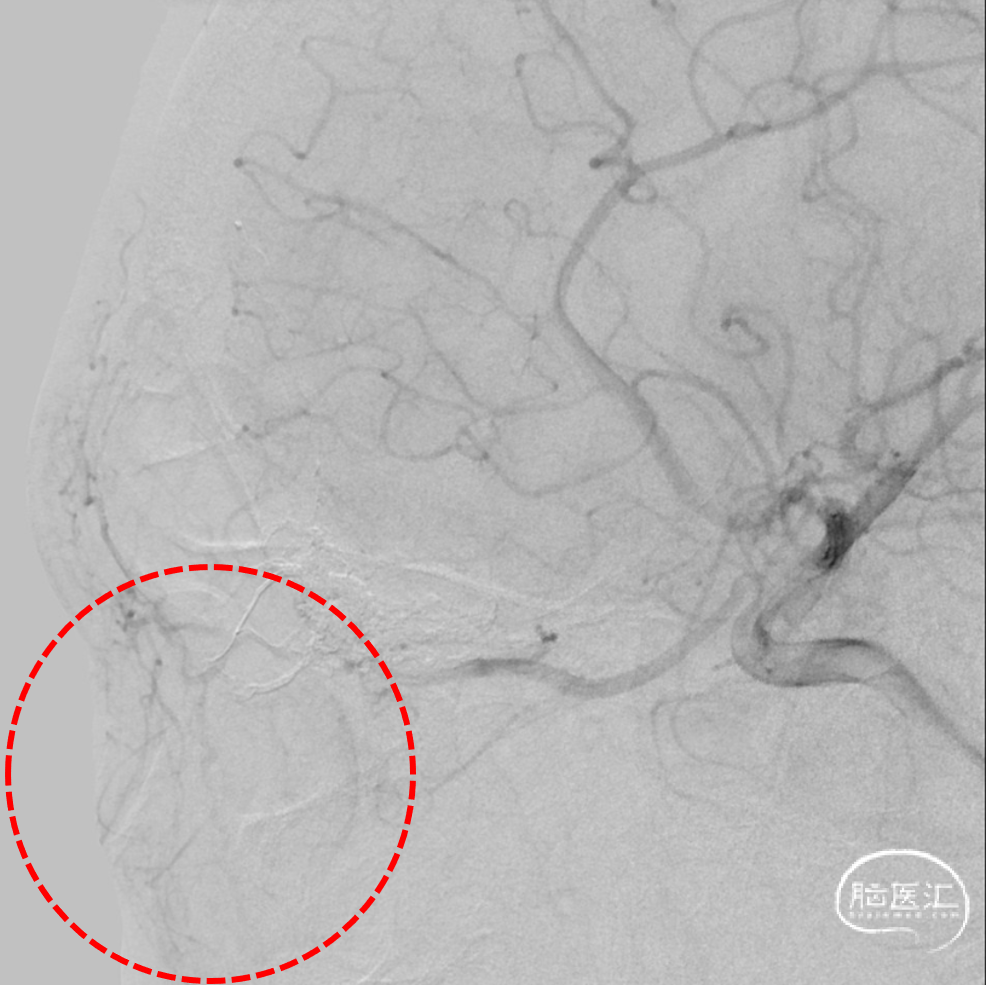

治疗经过